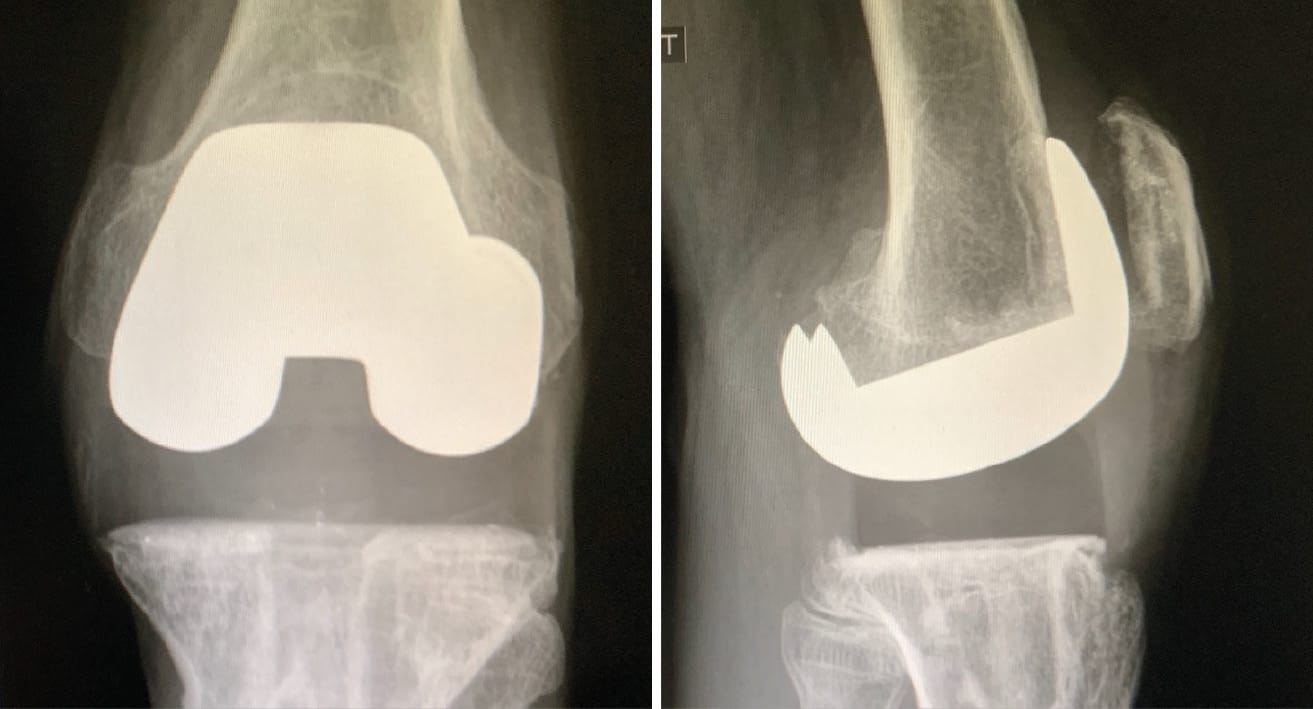

The inaugural “modern” total knee arthroplasty (TKA) designed and performed by Dr. Franck Gunston, a Canadian surgeon in 1968, marked the beginning of an era. Now six decades later, we can appreciate the extensive journey that has led to enhancements in both the longevity and functional outcomes of knee replacements (Figure 1). Advances in surgical techniques and implant design have been instrumental in improving patient satisfaction. Despite these improvements, literature reveals that dissatisfaction rates among patients post-TKA hover between 10 to 20% [1] DeFrance M, Scuderi G. Are 20% of Patients Actually Dissatisfied Following Total Knee Arthroplasty? A Systematic Review of the Literature. J Arthroplasty 2022:S0883-5403(22)00931-7. https://doi.org/10.1016/j.arth.2022.10.011. The primary avenues of research to diminish these statistics focus on the use of robotics and the pursuit of optimal alignment. Since the nascent stages of TKA, alignment has been a pivotal concern: In the 1980s, Insall & Hungerford presented divergent alignment philosophies—anatomical versus mechanical—which laid the groundwork for the myriad of alignment methods we see emerging today. Bellemans et al.’s introduction of the constitutional varus concept in 2012 [2] Bellemans J, Colyn W, Vandenneucker H, Victor J. The Chitranjan Ranawat award: is neutral mechanical alignment normal for all patients? The concept of constitutional varus. Clin Orthop 2012;470:45–53. https://doi.org/10.1007/s11999-011-1936-5., paved the way for a more “physiological TKA” preserving a minor degree of the original deformity in patients with preexisting varus conditions. John Insall posited that TKA was a soft tissue operation, underlining the significance of knee laxity on functional outcomes. The overarching goal of all alignment strategies remains consistent: obtaining a perfectly balanced knee.

Mechanical alignment (MA) in TKA aims for a straight alignment of 180° ± 2° along the mechanical axis of the lower limb. This axis extends from the center of the femoral head, through the knee, and to the center of the ankle—forming the Hip-Knee-Ankle angle. Precise cuts are made at 90° to both the femur’s and the tibia’s mechanical axes. (Figure 3) This surgical technique, outlined by Insall et al. in 1982, is widely regarded as the gold standard for TKA [4] Insall JN, Binazzi R, Soudry M, Mestriner LA. Total knee arthroplasty. Clin Orthop 1985:13–22.. The rationale for these perpendicular cuts is to ensure even load distribution across the prosthesis, thus reducing wear and risk of aseptic loosening. Nonetheless, this technique has been critiqued for its necessitation of ligament release, which can result in suboptimal gap balancing—potentially contributing to the dissatisfaction experienced by 10-20% of TKA patients. These challenges with gap balancing have led surgeons to explore new alignment strategies that better balance the gap while more closely approximating the patient’s native knee anatomy.